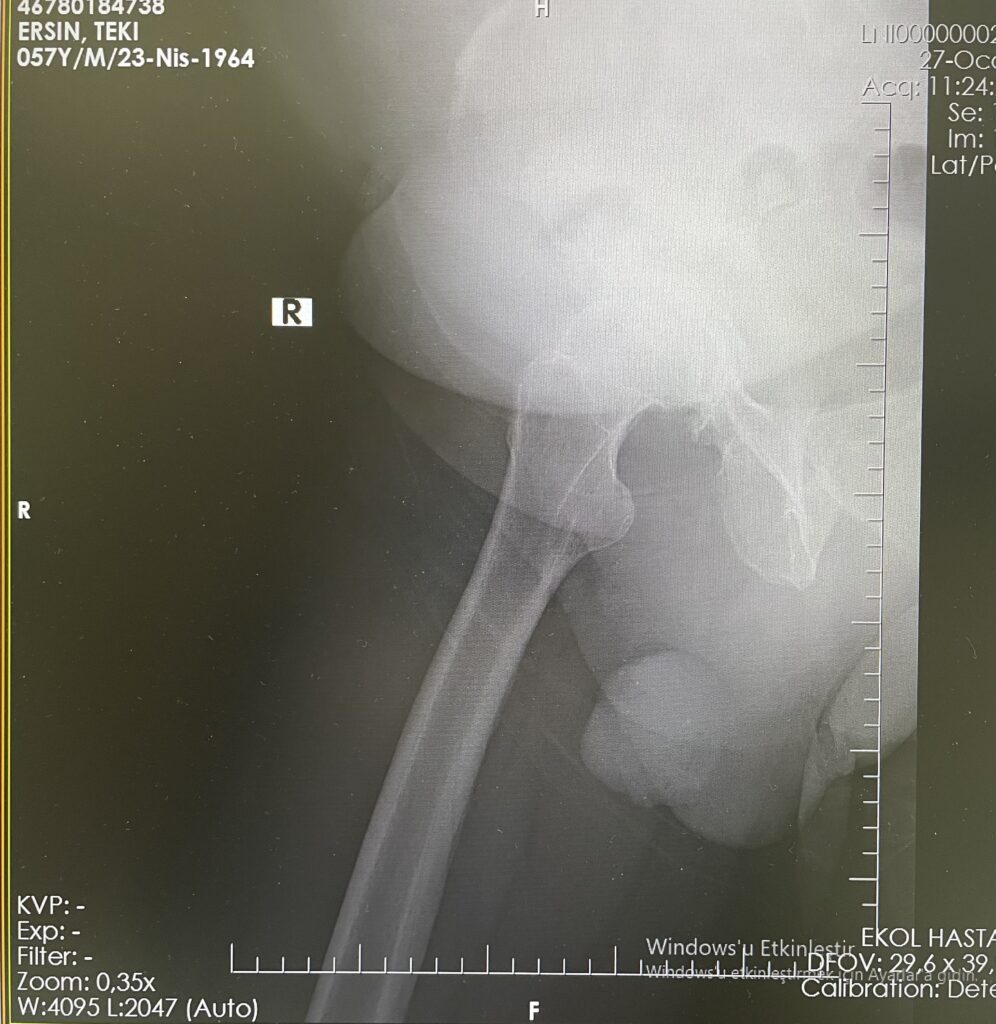

E.T.